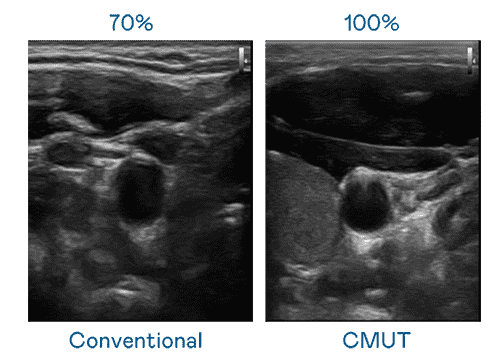

CMUT 技术是一种用电容式微机电元件来产生超音波讯号的技术。。。与传统 PZT 压电式技术相比,,,CMUT 频宽增加 30%,,,,更宽频的超音波讯号让影像解析度大幅提升,,,是实现高影像品质医疗超音波扫描、、、促进精准医疗发展的关键技术。。。

大频宽带来超清晰影像

超音波影像的解析度高低,,,首先取决于探头能发出的讯号频宽。。z6mg·人生就是博 CMUT 可提供高清晰的超音波讯号,,,,提供高频宽、、、、高灵敏度、、、、影像纹理细节更高的超音波影像,,,,协助医护人员缩短影像判读时间及利用精准的医疗影像进行诊断。。。。